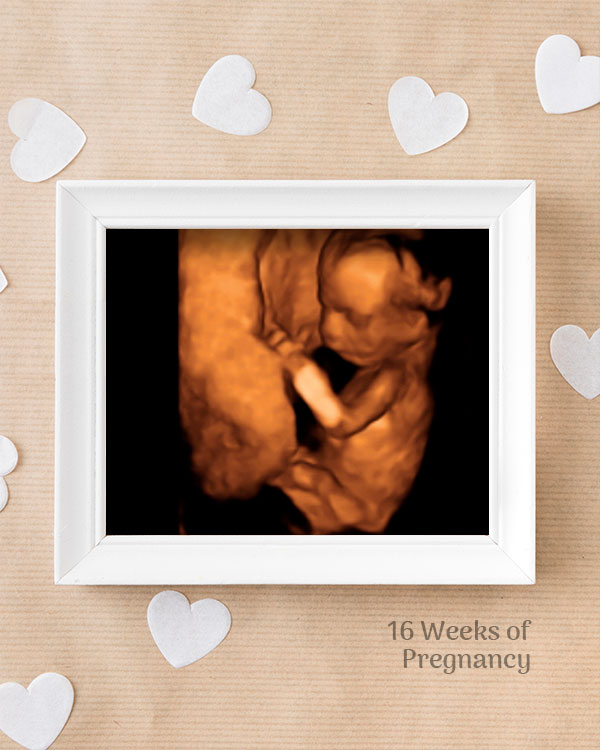

3D / 4D Baby Scan

Mediserv Diagnostics pioneered 4D scanning in the Malabar region. These advanced scans provide realistic images of the baby, allowing detailed evaluation of fetal structures and movements while creating a meaningful bonding experience for parents.